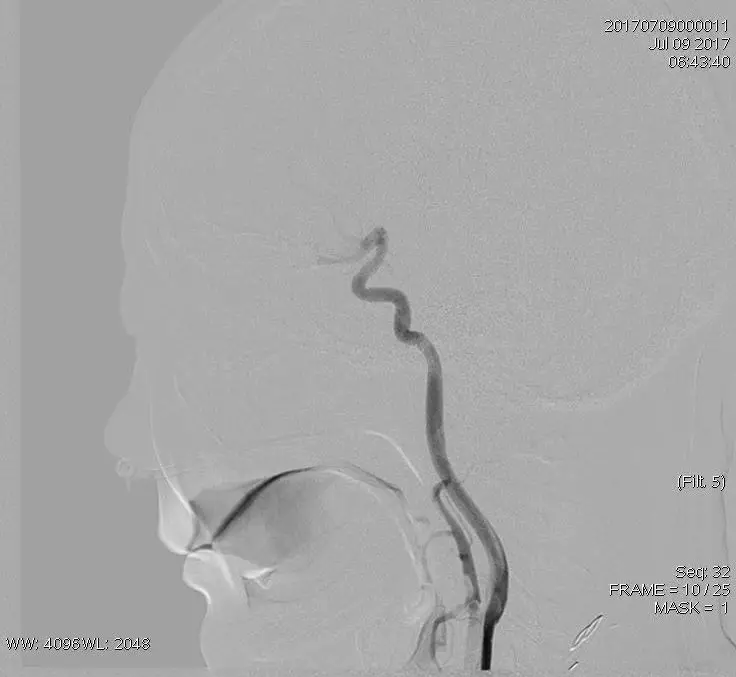

术后造影评估发现,血流速度良好。

取栓后造影:TICI 3级